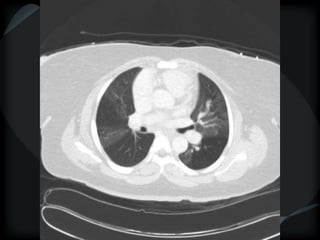

Reticular Pattern - NSIP

inflammation and fibrosis

 Predominantly basilar

 Significant ground glass

 Subpleural sparing low sensitivity, high specificity

 No honeycombing, some cystic change

 Traction Bronchiectasis

Diagnostic accuracy 50%

 Cellular NSIP

 Fibrotic NSIP

 Associated with CVD

 Undifferentiated CVD – T. King

NSIP- cellular

NSIP-fibrotic